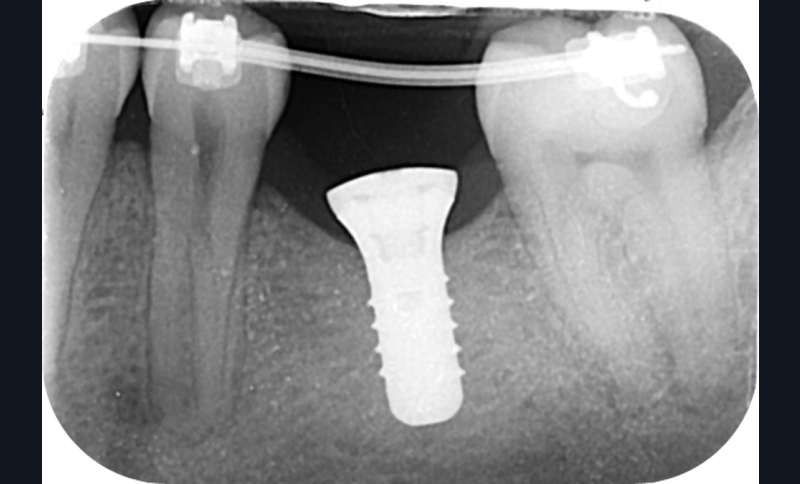

Cette version, quand elle se produit, modifie les espaces interdentaires et complique l’hygiène proximale des patients. Des caries peuvent alors se développer en interproximal sans que cela soit forcément visible à l’examen visuel (fig. 3 et 4). Les radios de type bite-wing (rétro-coronaires) prennent alors tout leur sens (fig. 5 et 6).

Le temps de l’ostéointégration, des versions ou migrations sont aussi possibles et le recours à des dispositifs de maintien de l’espace peut se révéler indispensable (fig. 22 et 23).